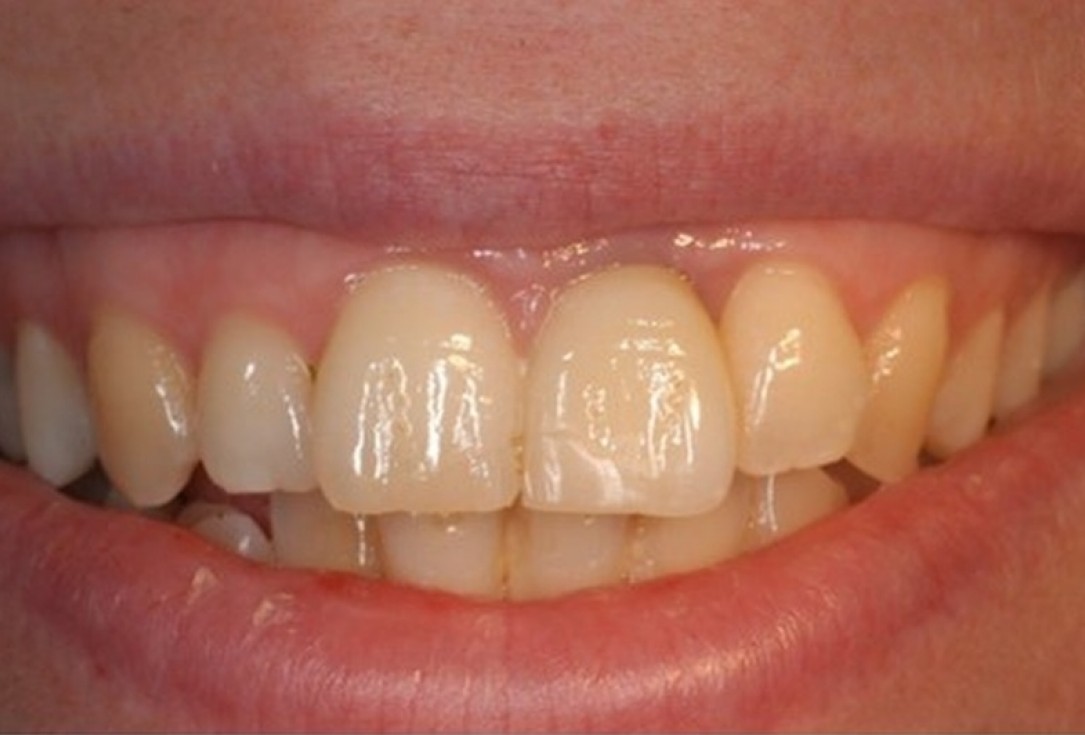

01/12 - Extraction of tooth 21 after endodontic treatmentTreatment of dehiscence defect with cerabone® & Jason® membrane - Dr. M. Steigmann

02/12 - Extraction of tooth 21 after endodontic treatmentTreatment of dehiscence defect with cerabone® & Jason® membrane - Dr. M. Steigmann